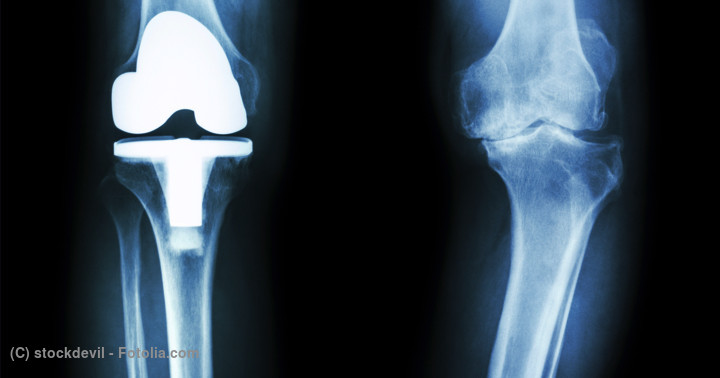

骨切り術 - 人工関節置換術

保存的治療で症状がコントロールできない場合などは手術になります。手術の選択肢としては骨切り術や人工関節置換術があります。